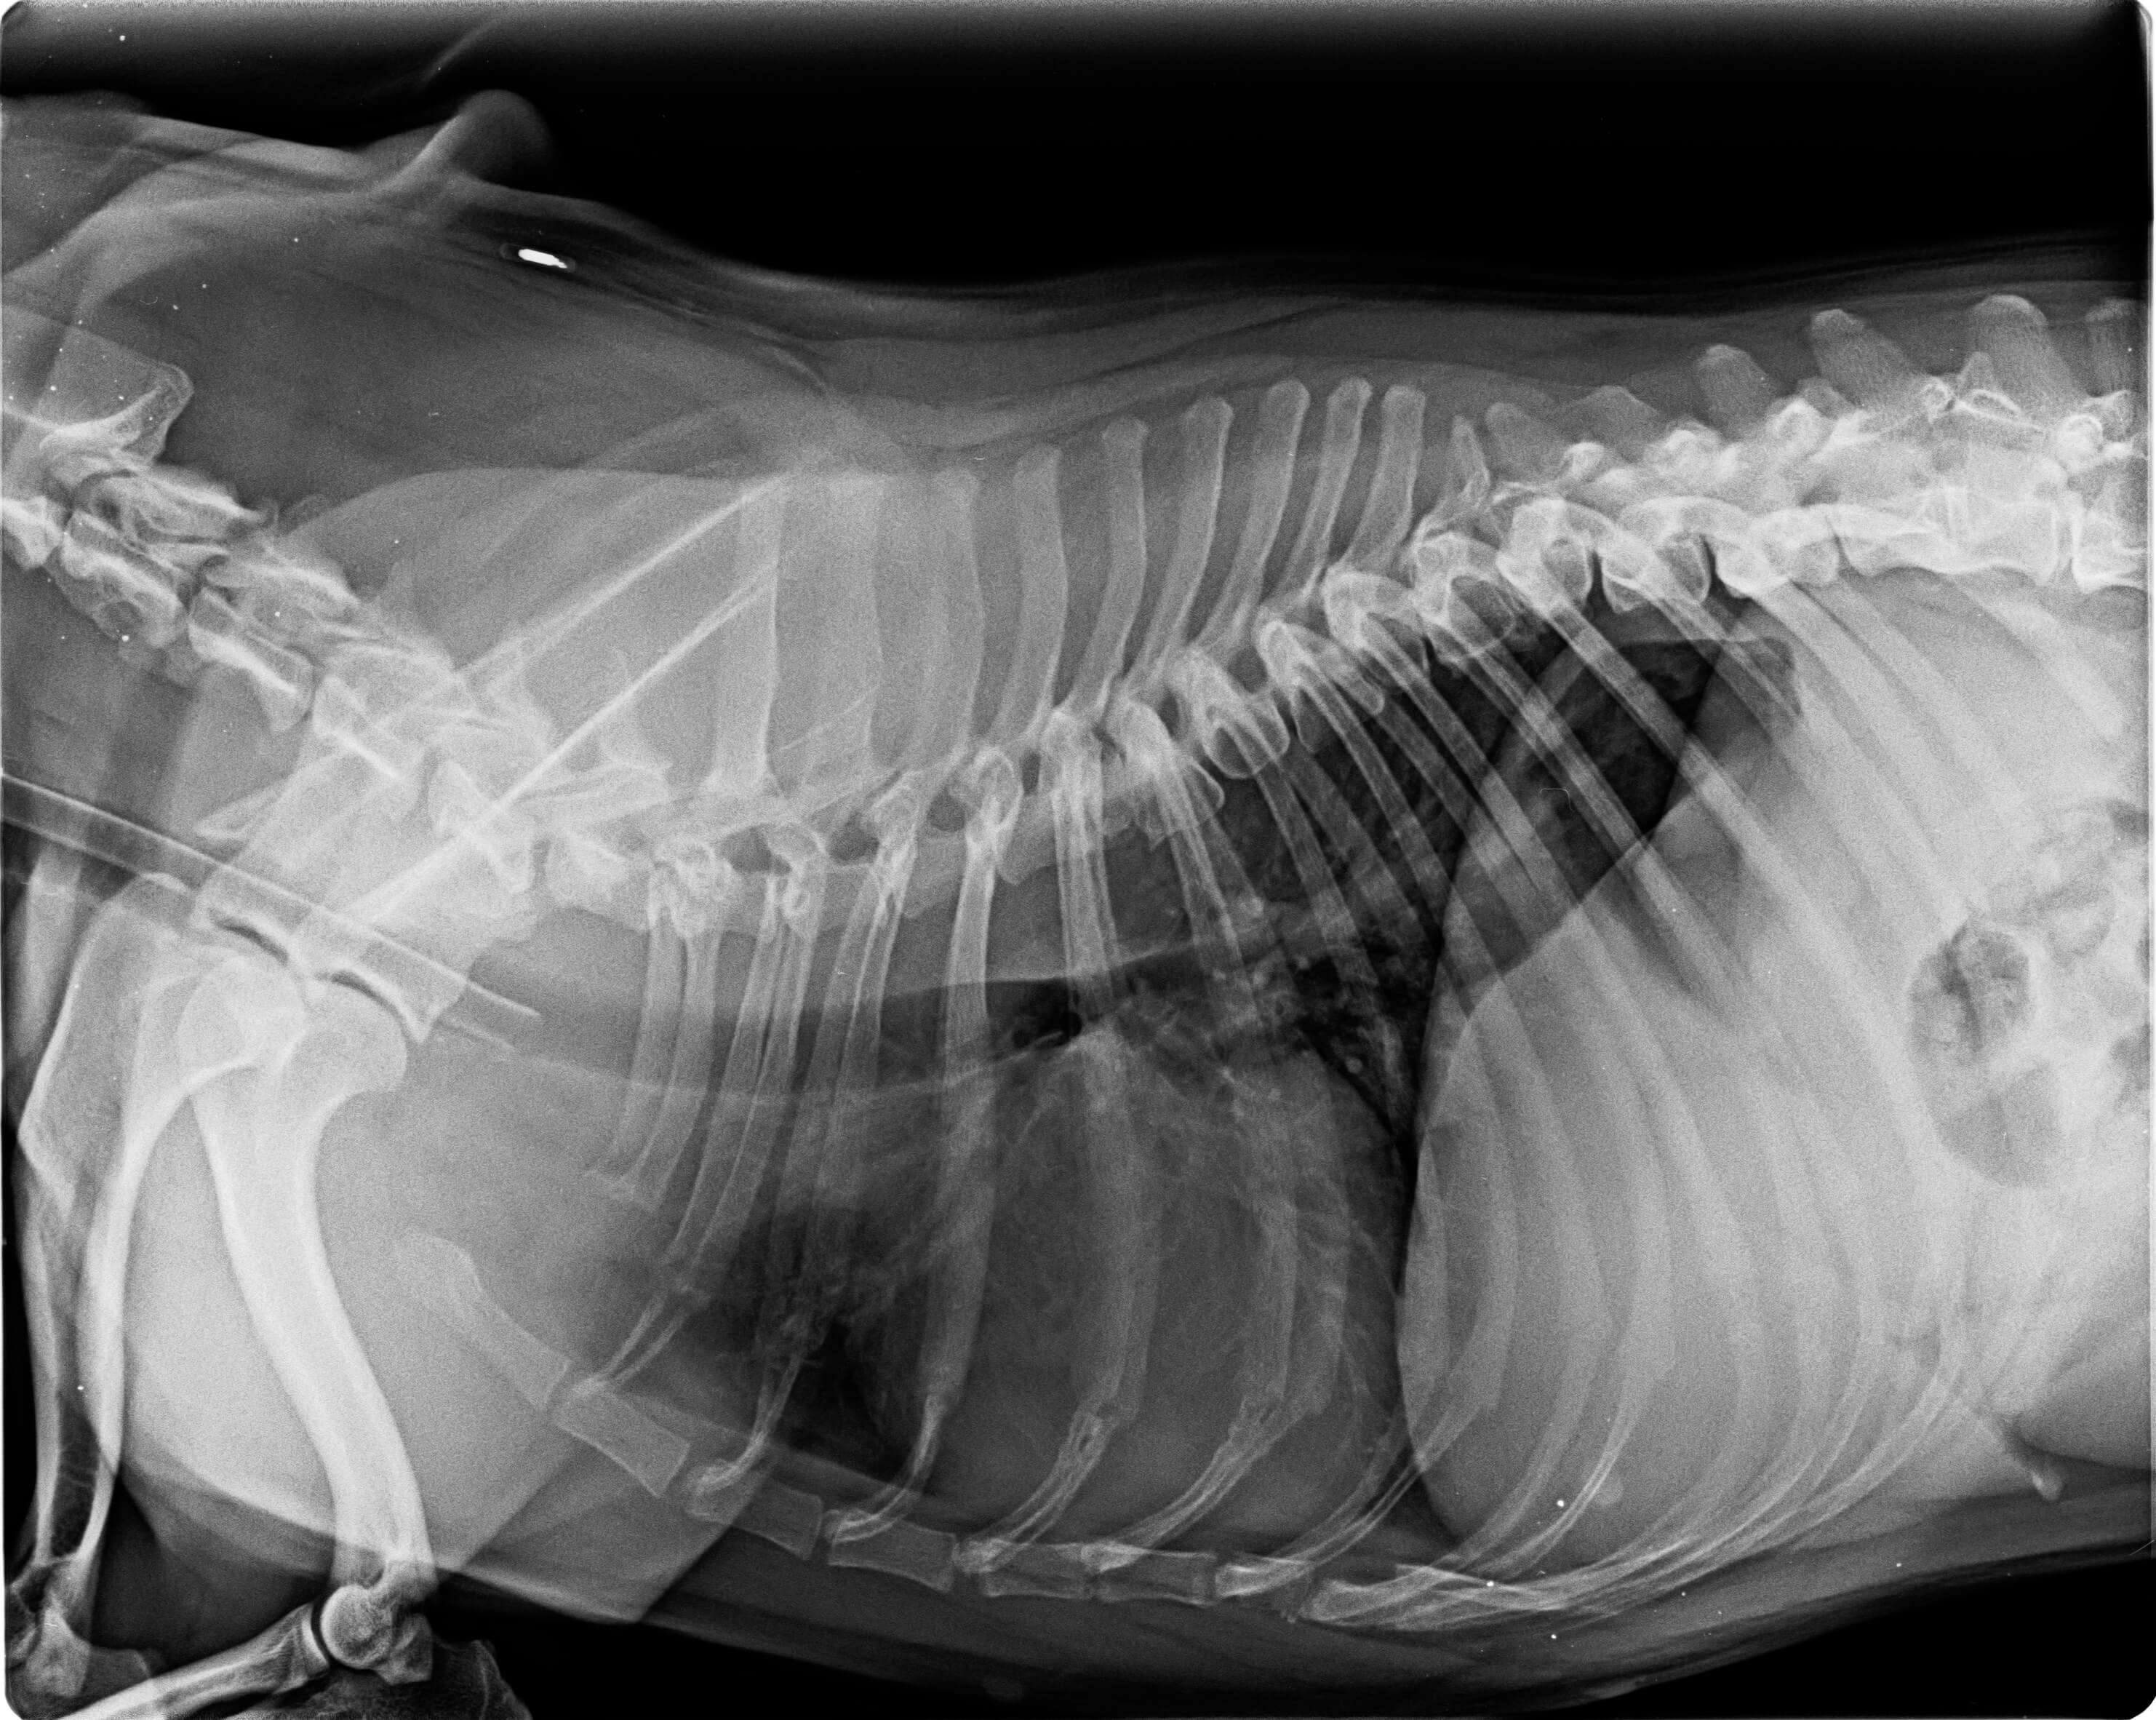

Bewegungsapparat

Missbildungen der Wirbelsäule und Problem des gesamten Bewegungsapparates führen häufig zu sehr schmerzhaften Symptomen bei Kurzschnauzern.

Viele dieser Probleme ergeben sich durch die züchterischen Merkmale, wodurch ein medizinischer Eingriff notwendig sein kann. In einigen Fällen kann eine konservative Behandlung ausreichen, sollte dies nicht der Fall sein, ist eine chirurgische Intervention notwendig. Zur Diagnosestellung stehen verschiedene bildgebende Verfahren zur Verfügung.